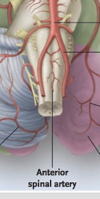

main blood supply to brainstem

basilar artery

branches off anterior spinal artery

paramedian arteries

as medulla gets closer to spinal cord, what artery starts giving off paramedial branches

anterior spinal artery